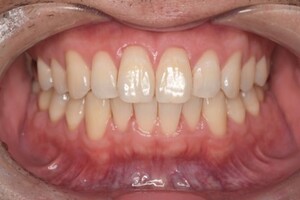

CASE 5

Before

After

基本情報

| 年齢・性別 | 19歳・女性 |

|---|---|

| 主訴 | 定期検診 |

| 治療内容 | PMTC |

| 治療期間 | 30分 |

| 治療費 | 5,500円 |

| リスク・副作用 | 知覚過敏 |

| 治療方針 | スケーリングしてから着色を除去しました。着色は一度綺麗に落としても再度付着するため、今後は定期的なクリーニングを行います。 |

| 担当者所見 | 歯ぐきに色素が沈着しているためガムピーリングとホワイトニングを行うことで、より明るく見えるようになります。 |